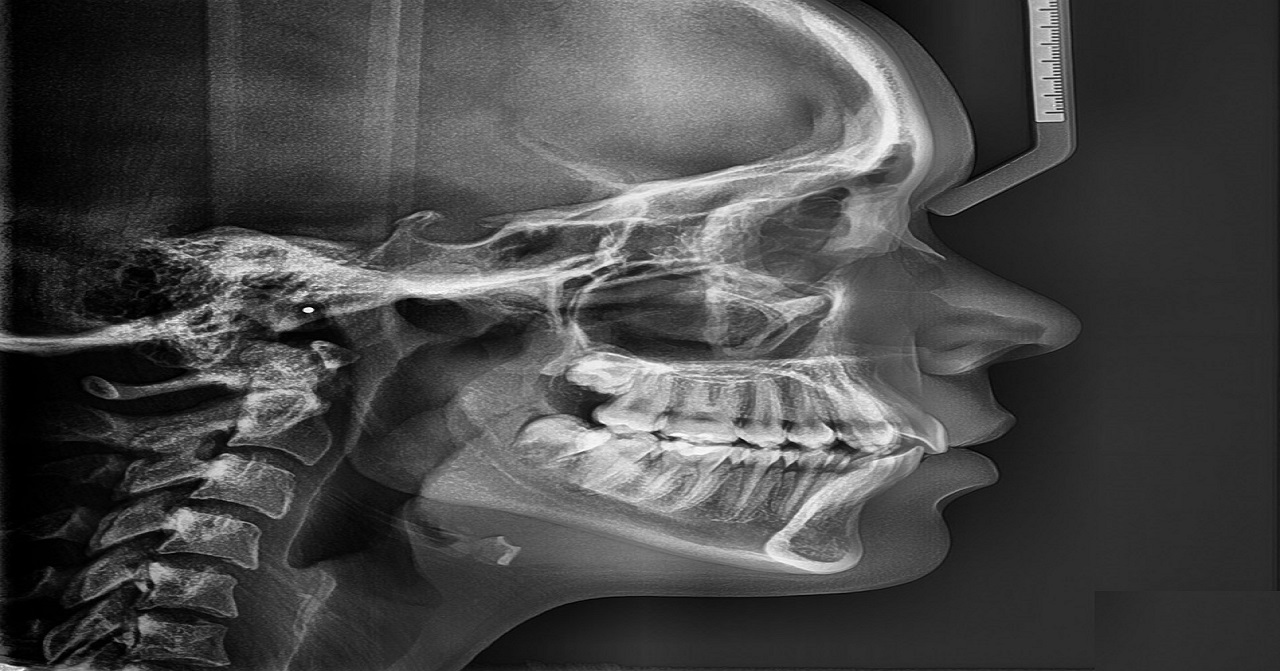

Teleradiografia Lateral de Craneo

Es una radiografía lateral de la cara donde haz del rayo X es perpendicular a la película y al plano sagital, mayormente utilizada para traumatismos craneales, cefalometría en ortodoncia, implantes, alteración del desarrollo, tejidos blandos, nasofaríngeos, senos paranasales, osteogénesis imperfecta, mieloma múltiple.